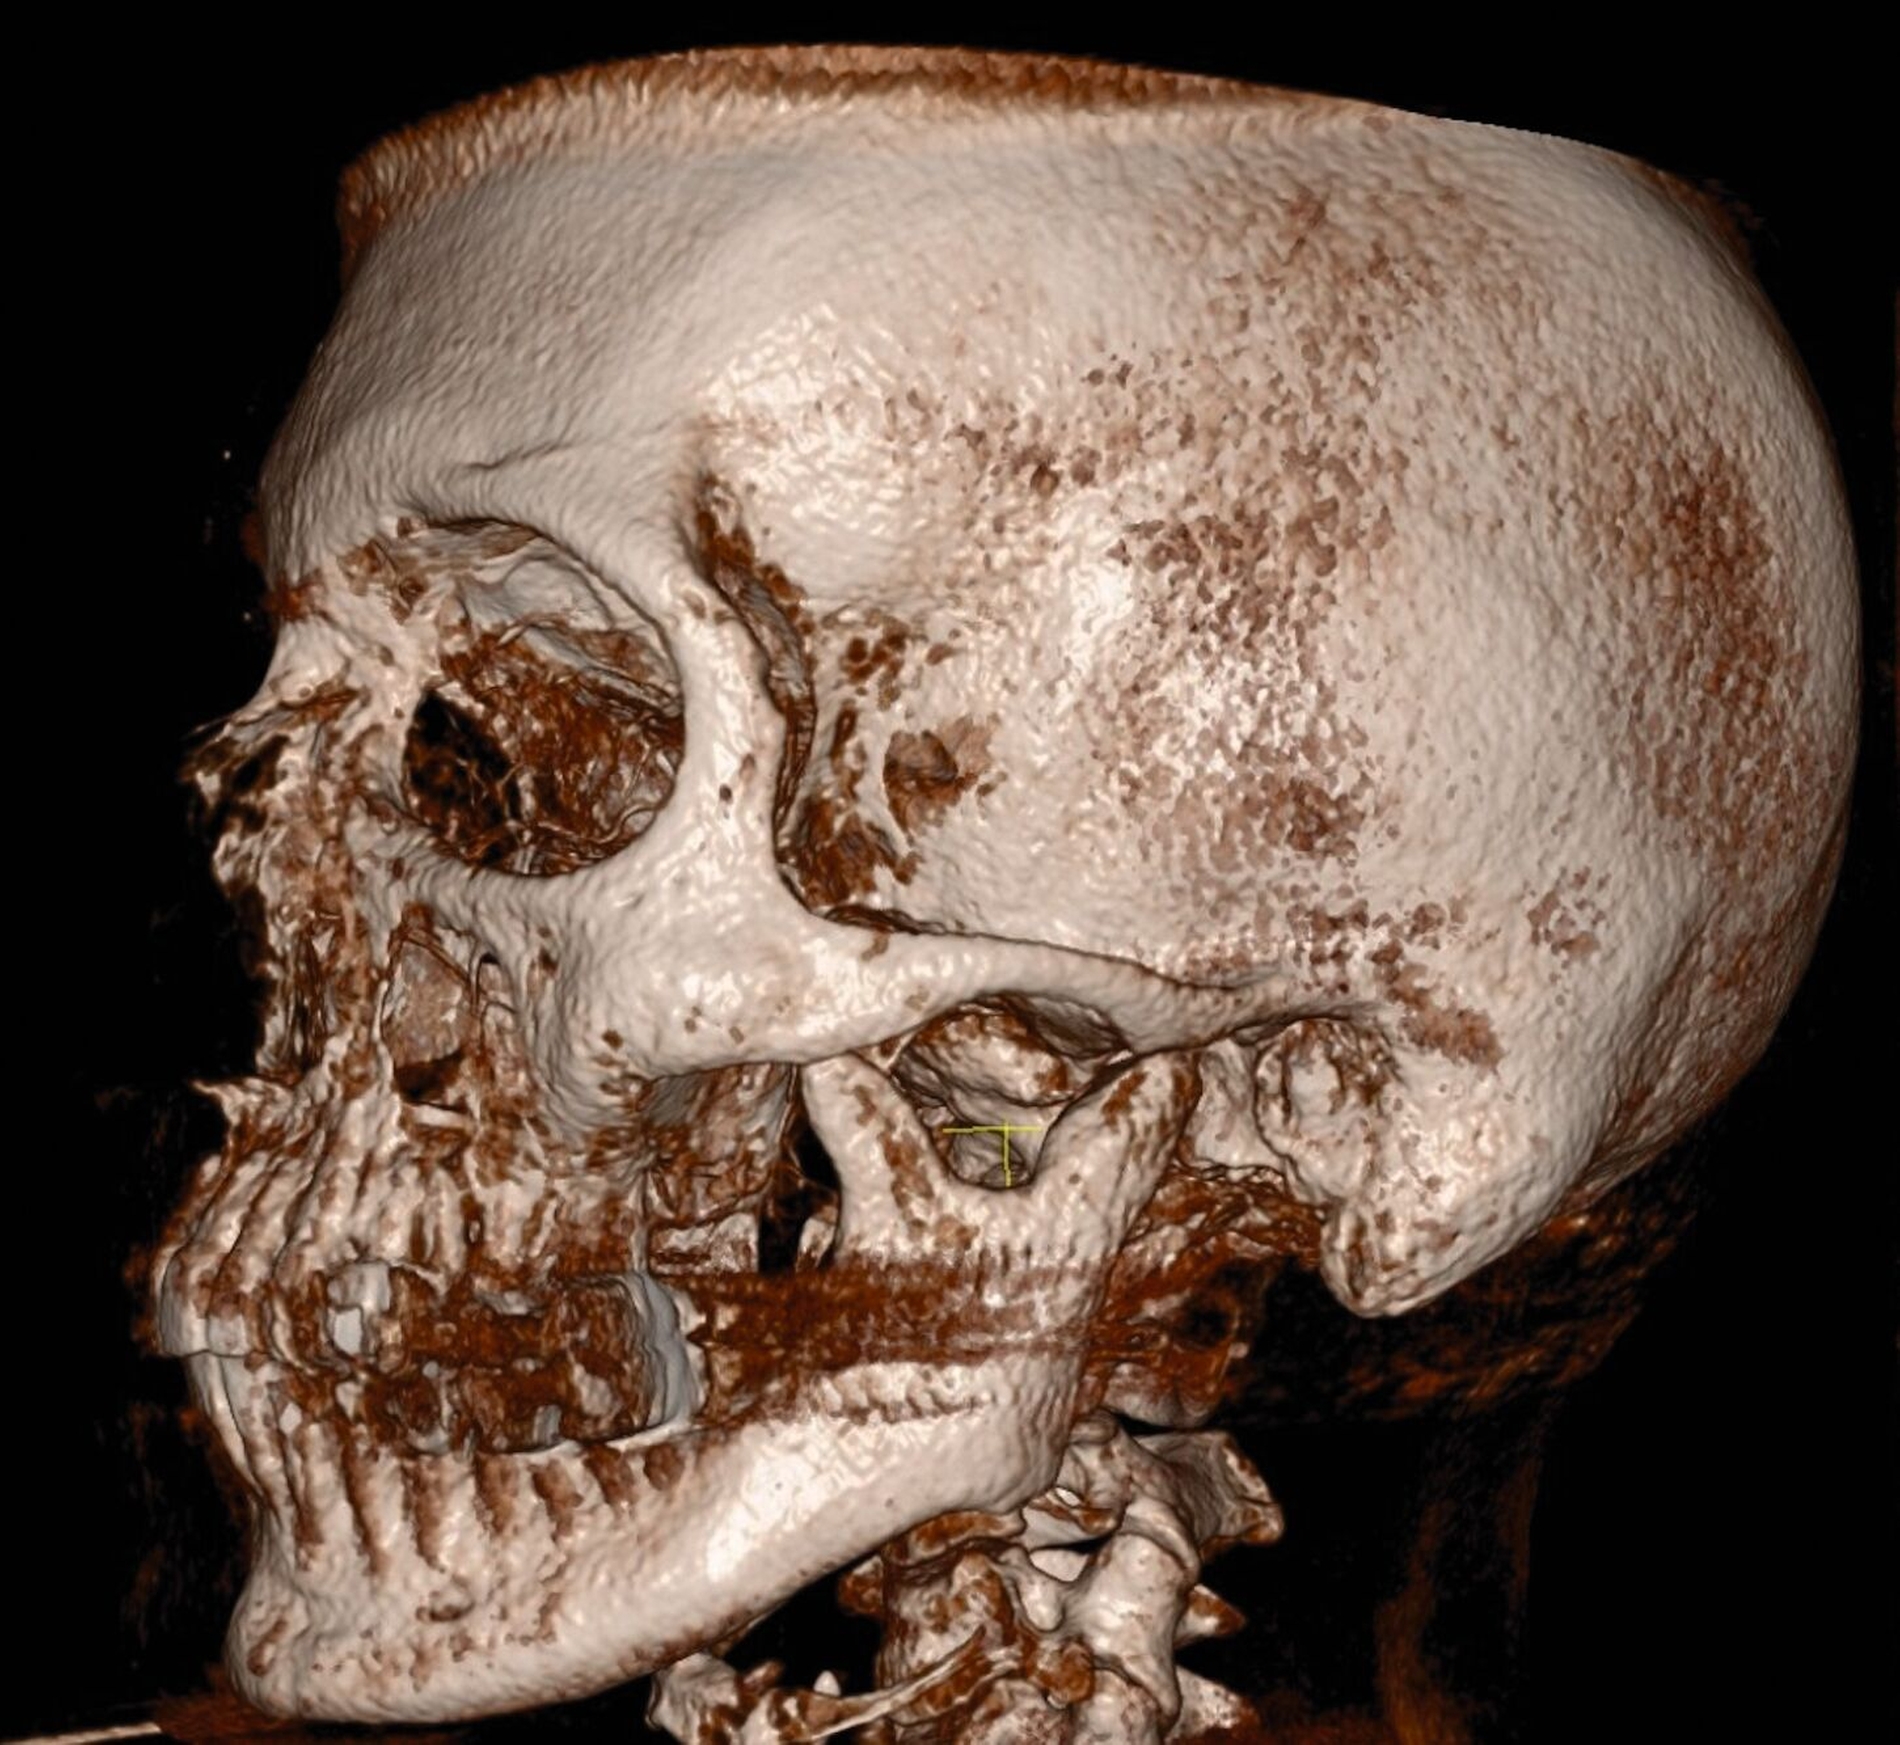

Anamnestisch waren bei ihr im März 2021 eine beidseitige Collumfraktur mit begleitendem frontoffenem Biss und eine Corpusfraktur im Unterkiefer infolge eines synkopalen Sturzes nach einer COVID-19-Impfung aufgetreten. Da das linke Collum in Fehlstellung verheilte, erfolgte alio loco eine operative Revision mit Osteosynthese (Abbildung 1). Das Metall wurde im April 2022 entfernt. Der Hauszahnarzt führte daraufhin im Verlauf eine Aligner-Therapie durch, um die immer noch fehlerhafte Okklusion zu optimieren sowie diverse Dreh- und Kippstände zu beseitigen.

Im Rahmen der Konsultation der Mund-, Kiefer- und Gesichtschirurgie und der Kieferorthopädie erfolgte eine erneute radiologische Bildgebung (Abbildung 4). Die Patientin wurde im Anschluss beraten, dass eine Re-Osteotomie des ehemals frakturierten und nun in Fehlstellung verheilten Collumsegments links ihr Okklusionsproblem adäquat lösen könnte. Ebenso sei eine orthognathe Umstellungsosteotomie möglich. Nach ausführlicher Aufklärung entschied sich die Patientin allerdings gegen eine chirurgisch-kieferorthopädische und für eine rein prothetische Lösung. Die Patientin hatte derart Angst vor einem erneuten chirurgischen Eingriff, dass sie selbst die Aussicht auf eine längere und invasivere prothetische Behandlungsphase nicht abschreckte.